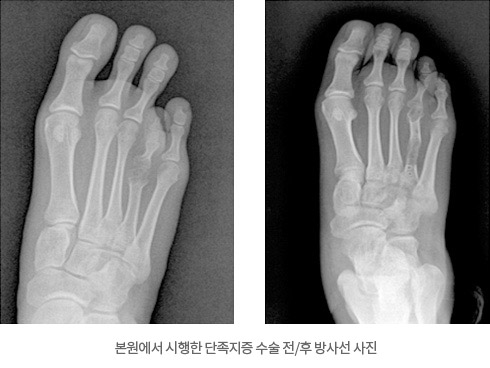

- └ 단족지증

단족지증